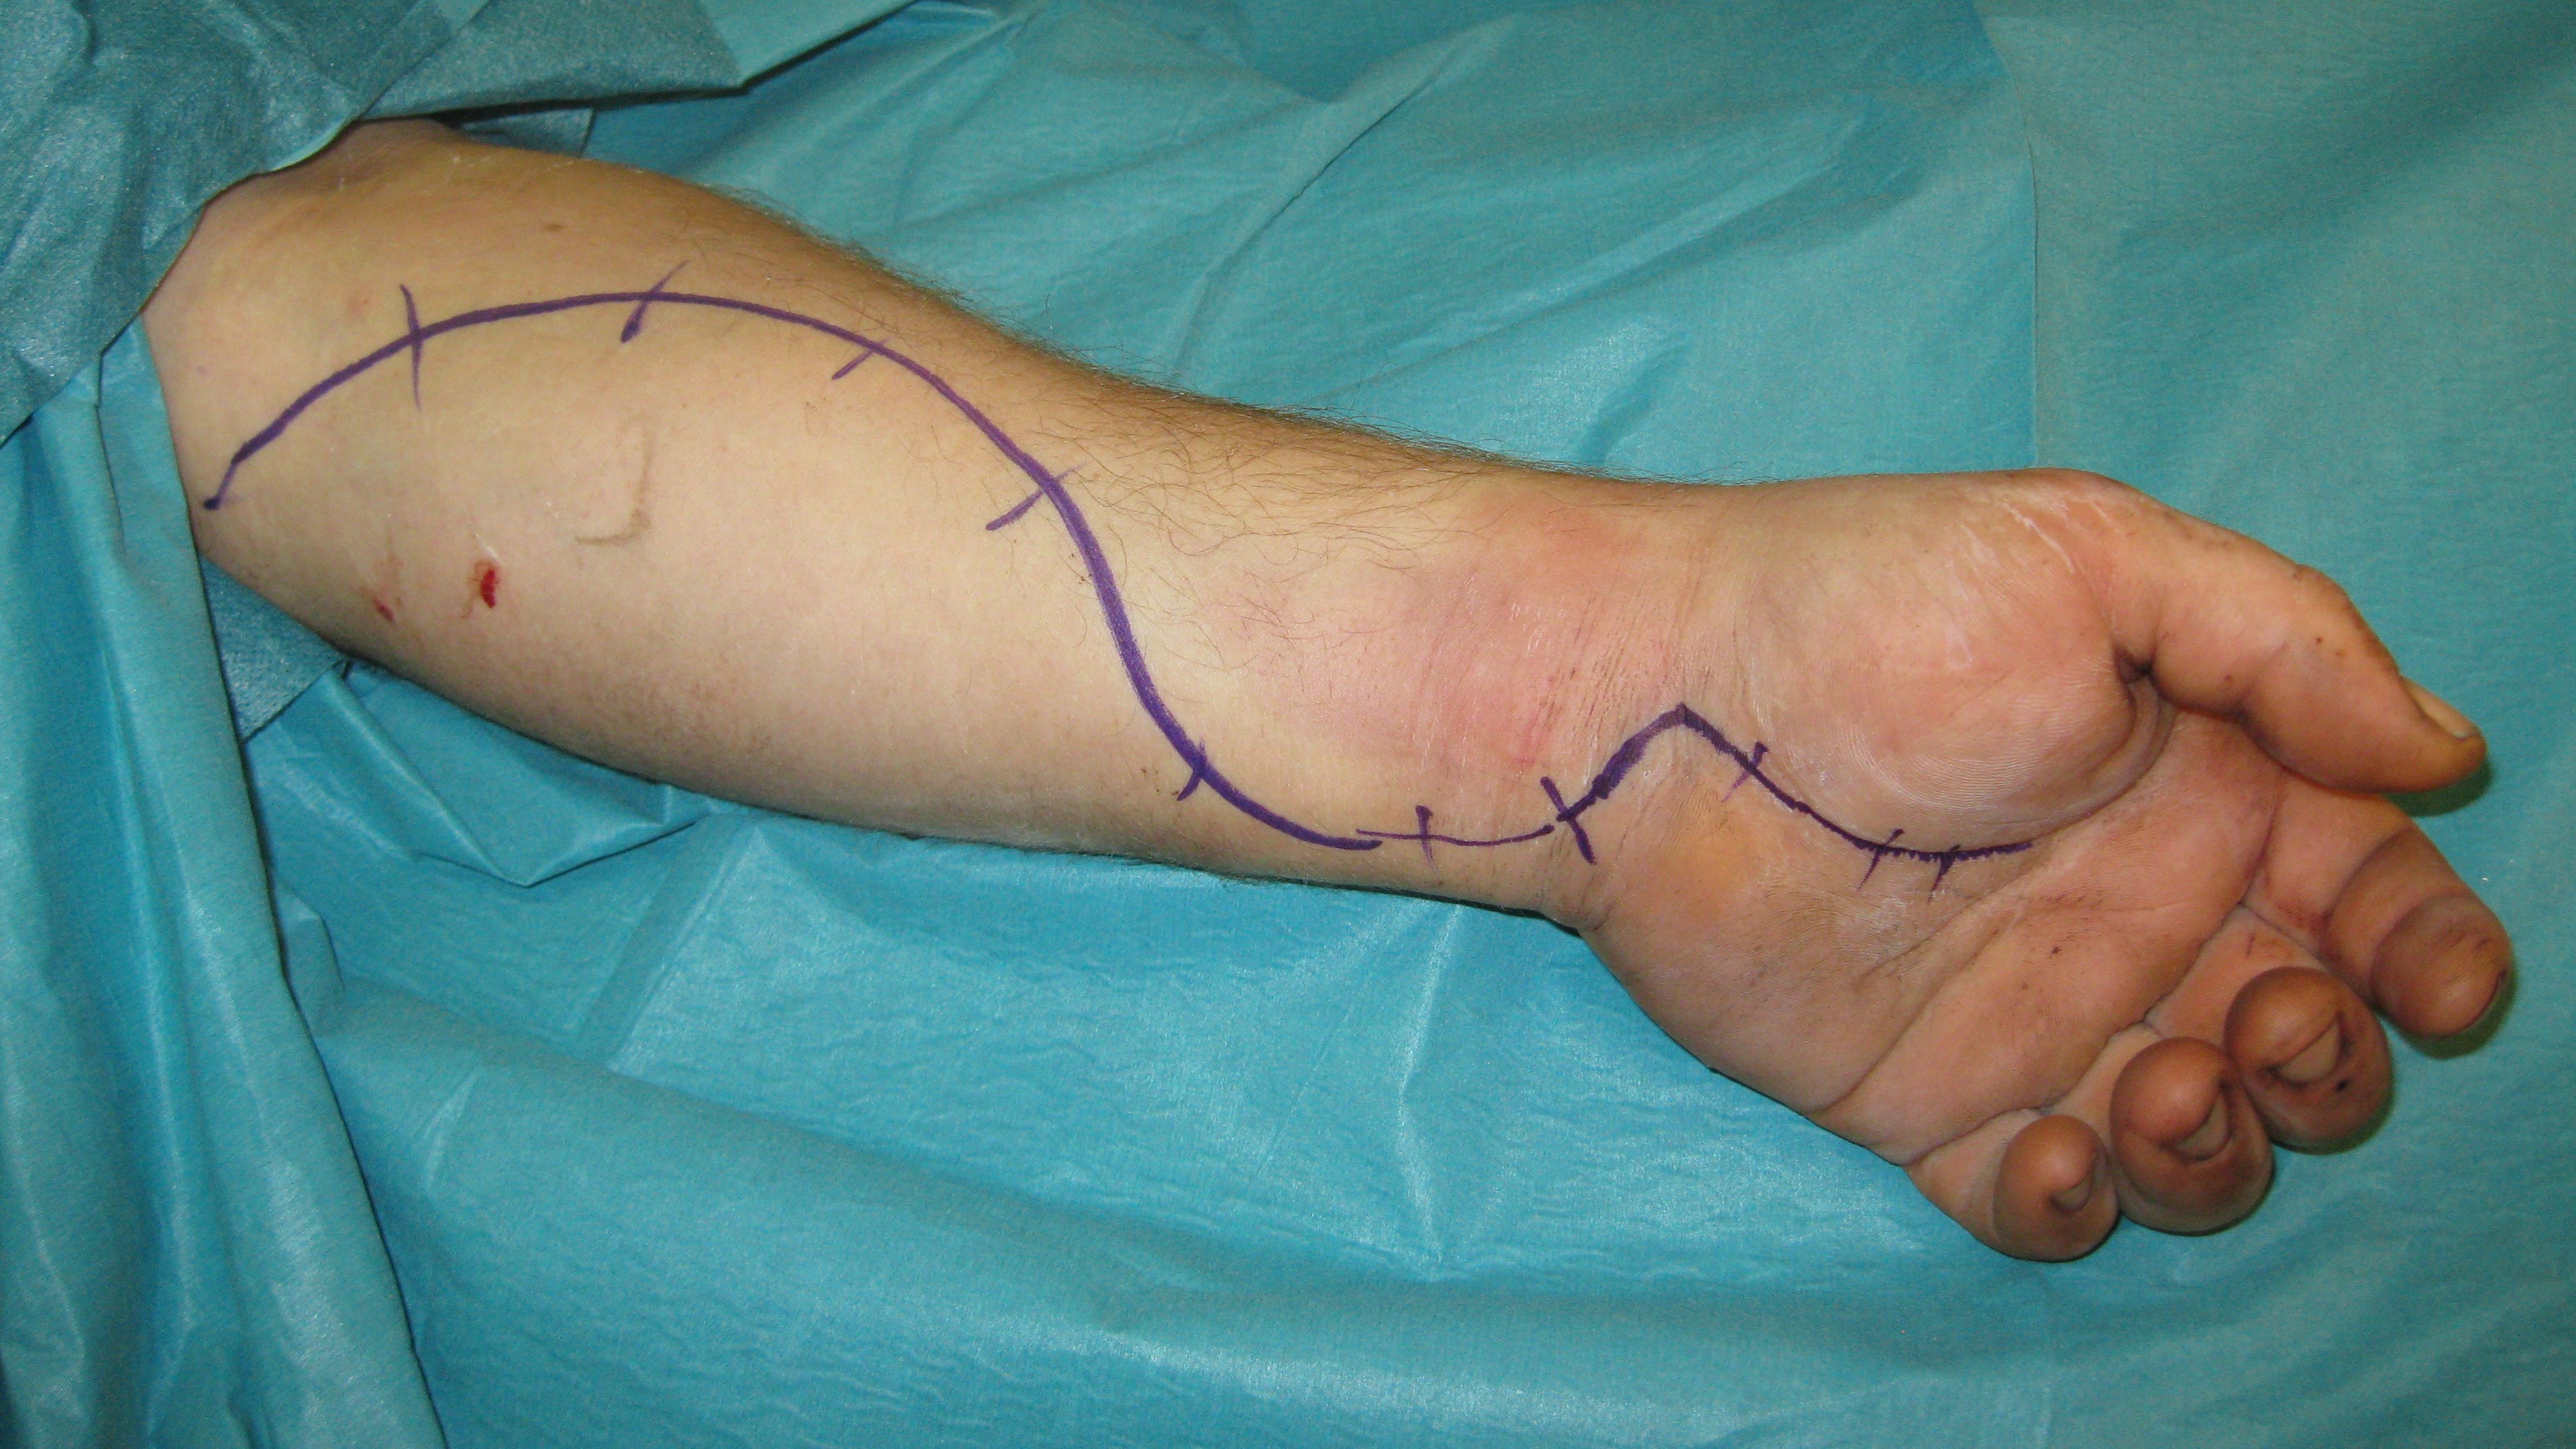

Behandling

Behandlingen är att det avgränsade rummets väggar, dvs. att fascior öppnas kirurgiskt. Många gånger sväller då musklerna fram och huden kan inte slutas. Man får då dra ihop såret så gått det går utan för mycket spänning för att sedan sluta såret när musklerna svällt av. Det finns även teknik för att hålla ihop och successivt sluta sårkanterna mha av ståltråd eller elastiska band.

Hudtransplantat kan senare behövas. När det gäller underarmen finns tre kompartment och både extensor och flexormuskulatur kan drabbas. I handen finns ett tiotal slutna kompartment som alla måste öppnas kirurgiskt om kompartment syndrom misstänks i denna region.

Observera att vid circumferenta brännskador finns överhängande risk för cirkulationsstörning och kompartmentsyndrom! I dessa lägen kan det vara aktuellt med fasciotomier och/eller escharotomier (längsgående snitt i handrygg samt fingrarnas lateralsidor) för att sänka trycket. Kontrollera funktion och status distalt om skadan.